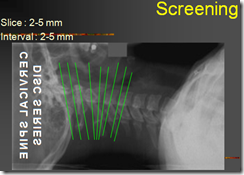

Slice thickness : 2 – 5 mm

Slice Interval : 2 – 5 mm contiguous (pitch=1)

Gantry Tilt : Paralel diskus, (Utk reform gantry tdk disudutkan), untuk sreening/area luas dg teknik “corpus-FIV-Disk”